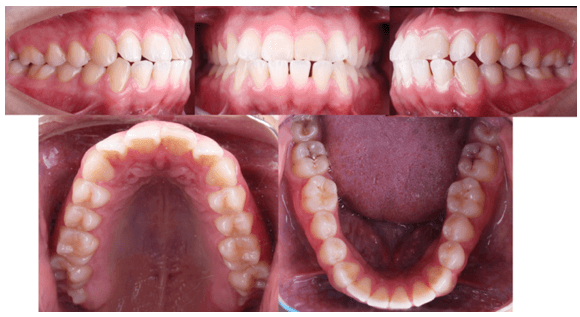

A la evaluacion intraoral presentaba deglusion atipica y una maloclusion molar clase III bilateral, clase II canina del lado derecho y clase III canina del lado izquierdo. Forma de arcada cuadrada en superior y ovoide en inferior. Biprotrusion dental. Presencia de OD 18, 28, 38, 48 erupcionados. Tremas de 3-3 en el maxilar inferior. Mordida cruzada anterior. Overjet de -1 mm. Overbite 0mm.

Fig 2. Fotografias intraorales